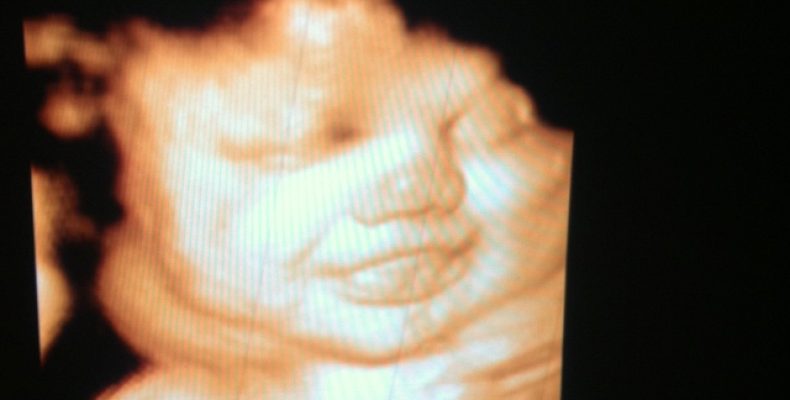

12 недель: Ваш малыш размером с лайм и уже вовсю строит рожицы

Вы еще не чувствуете никаких шевелений, живот только начал намекать на округлость, а внутри вас уже полным ходом идет грандиозная стройка. Первый триместр подходит к концу, и это не просто календарная дата, а мощнейший...